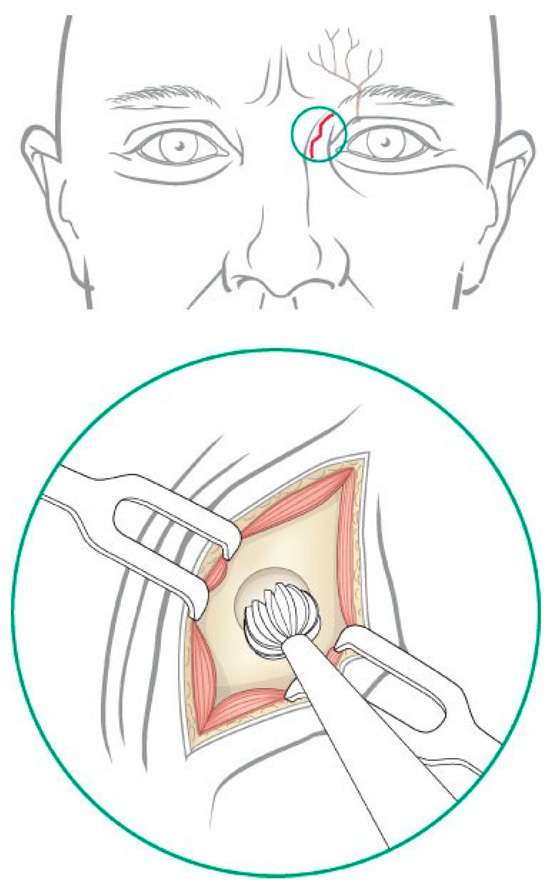

Frontal Sinus Trephination

Trephination and endoscopic visualization of the fron- tal sinus can be useful to assess the frontal recess as well as the extent of any posterior table injury. Appropriate consent is obtained for the procedure including the risks of bleeding, infection, paresthesia, and poor aes- thetic result. After infiltration of local anesthesia, a 1.0- to 1.5-cm skin incision is placed midway between the medial canthus and the glabella, ~1 cm inferior to the brow (Figure 9). The incision is best hidden by placing it inferior and deep to the curve of the forehead. A small V-shaped relaxing incision can be added to reduce the risk of scar contracture and webbing. The supratro- chlear neurovascular pedicle is located deep to the medial aspect of the brow and should be protected while the dissection is carried down to the periosteum. Although some authors have suggested placing the incision within the medial brow, this should be avoided because it places the supratrochlear neurovascular pedicle at greater risk and may result in injury to the hair follicles of the eyebrow. A guarded micropoint monopolar electrocautery can then be used to dissect through the soft tissues and onto the frontal bone. The location of the frontal sinus is confirmed on the CT scan (or with navigation if desired), and a small cutting burr is used to open a 4- to 5-mm frontal sinusotomy ~1 cm medial and inferior to the medial brow (Figure 9 inset). The mucosa is incised sharply, and the sinus can be suctioned free of any blood or mucus. The posterior table and nasofrontal recess can be examined with a 0- degree and/or 30-degree endoscope for any evidence of mucosal laceration or hematoma. A Valsalva maneuver can assist with the diagnosis of a CSF leak. Flexible pediatric bronchoscopes can be used to visualize the lateral aspects of the frontal sinus, but they are more cumbersome. Fluorescein or methylene blue have been instilled into the sinus to assess frontal recess obstruc- tion. However, dye materials make visualization of the sinus much more difficult (particularly methylene blue), and passage of the dye into the nose does not rule out the presence of a fracture or assess the long-term risk of frontal recess stenosis. The author does not recommend this technique. Once the examination has been com- pleted, the skin and soft tissue are closed meticulously in layers.

Figure 9.

Incisions used for trephination of the left frontal sinus. Caution must be used to avoid injury to the supratro- chlear neurovascular pedicle.